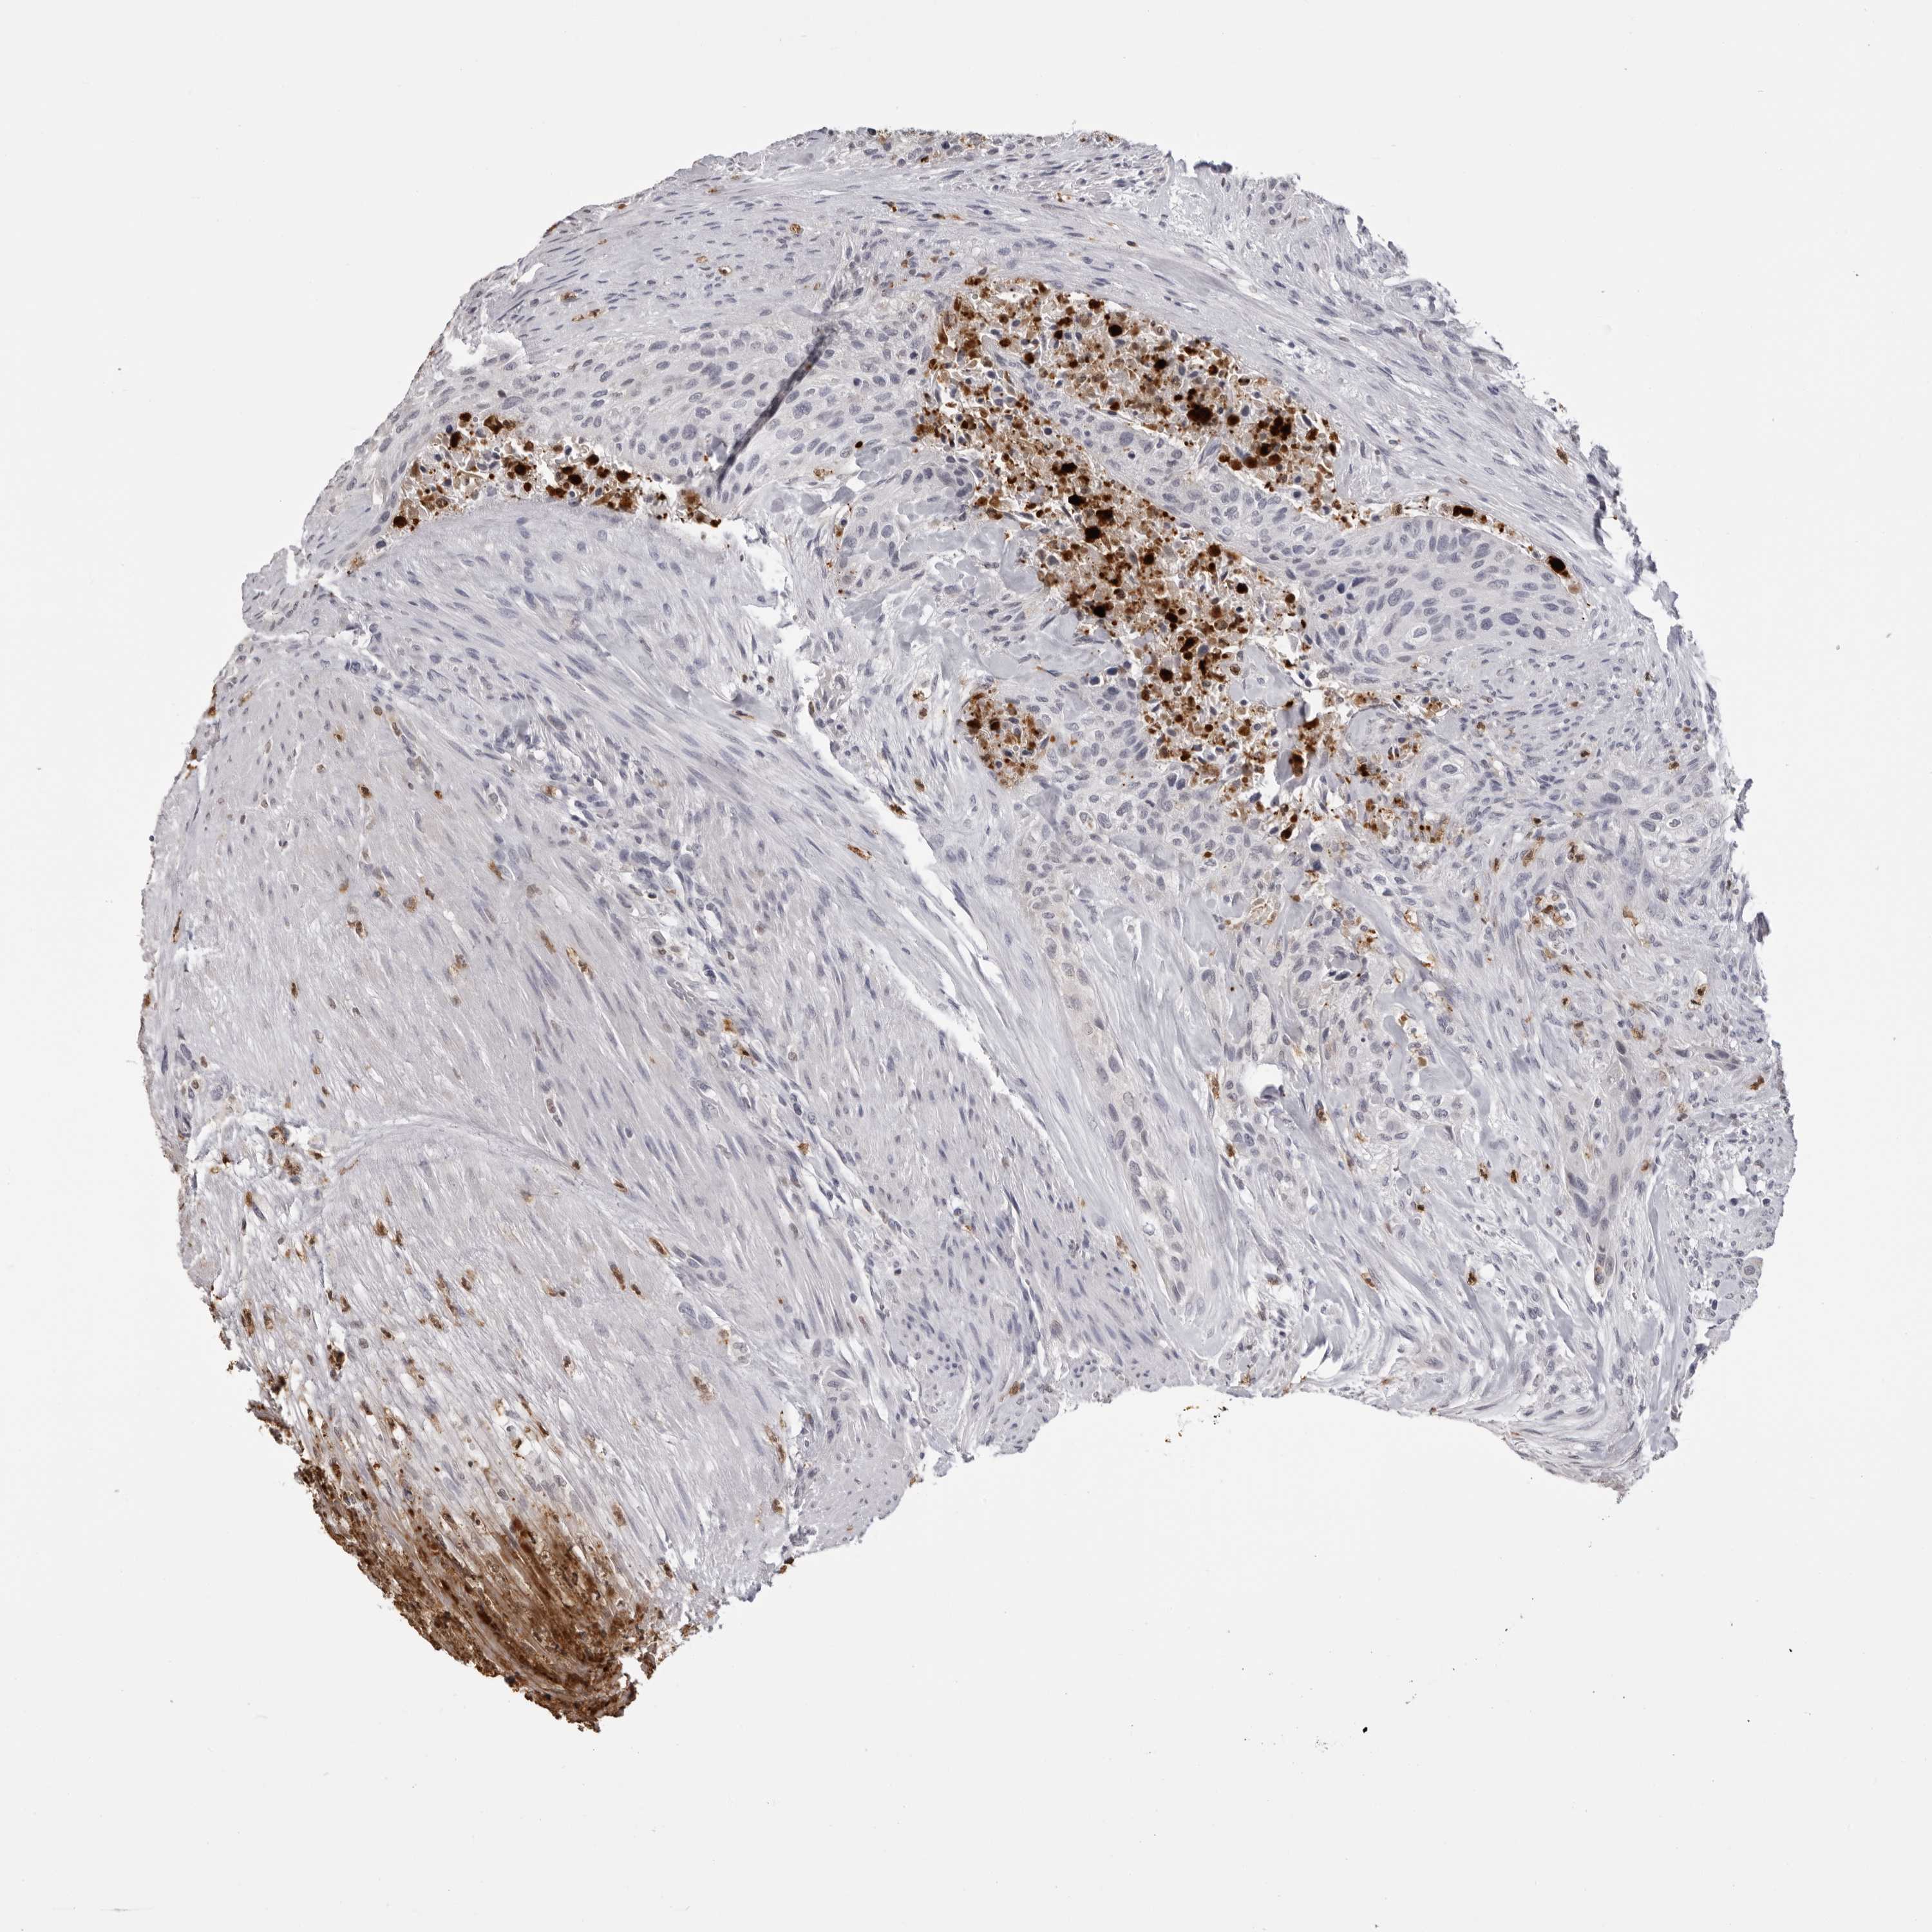

UROTHELIAL CANCER - Protein expressioni

A mouse-over function shows sample information and annotation data. Click on an image to view it in a full screen mode. Samples can be filtered based on level of antibody staining by selecting one or several of the following categories: high, medium, low and not detected. The assay and annotation is described here.

Note that samples used for immunohistochemistry by the Human Protein Atlas do not correspond to samples in the TCGA dataset.

Antibody stainingi

Antibody staining in the annotated cell types in the current human tissue is reported as not detected, low, medium, or high, based on conventional immunohistochemistry profiling in selected tissues. This score is based on the combination of the staining intensity and fraction of stained cells.

Each image is clickable and will lead to virtual microscopy that enables deeper exploration of all samples and also displays staining intensity scores, fraction scores and subcellular localization as well as patient and tissue information for each sample.

Antibody CAB025657

Staining

High

Medium

Low

Not detected

Intensity

Strong

Moderate

Weak

Negative

Quantity

>75%

75%-25%

<25%

None

Location

Nuclear

Cytoplasmic/membranous

Cytoplasmic/membranous,nuclear

Urothelial carcinoma, Low grade

Urothelial carcinoma, High grade